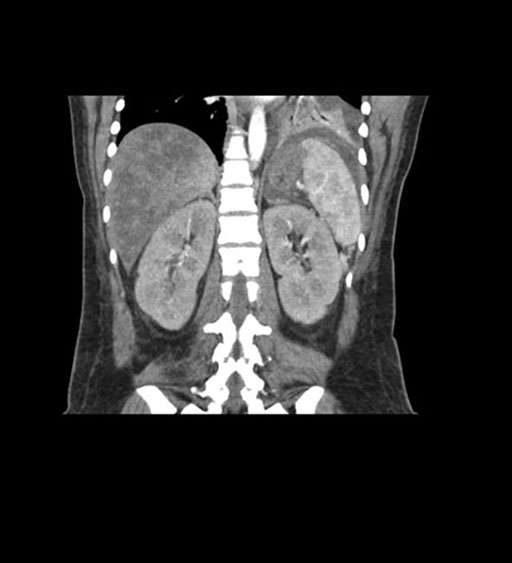

Imaging Analysis

Look through the patient's CT scan to identify any areas of concern for the necessary procedure.

Coronal Arterial